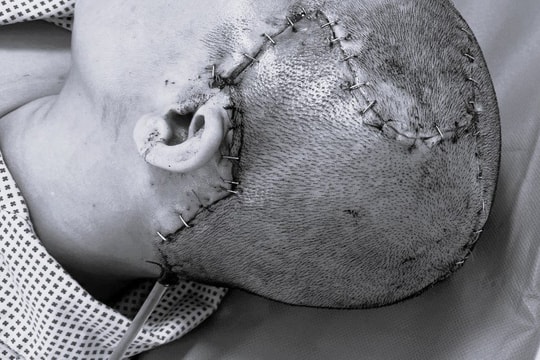

Thuốc An Cung Rùa Vàng là sản phẩm của Công ty TNHH Dược phẩm Thường Thái Diên An, tỉnh Thiểm Tây, Trung Quốc. Tiền thân là nhà máy chế tạo thuốc Bát lộ quân, đây là xí nghiệp sản xuất thuốc Đông y thành phẩm lớn nhất vùng Thiểm Bắc, cũng là xí nghiệp sản xuất thuốc duy nhất tại Diên An. Từ ngày thành lập đến nay, nhà máy luôn tuân thủ nguyên tắc “Nguyên liệu thật, chất lượng hàng đầu, thành thực tin cậy”, có uy tín tốt trong và ngoài nước. Sản phẩm được nhập khẩu về Việt Nam và được Cục Quản lý Dược, Bộ Y tế cấp phép lưu hành theo tiêu chuẩn CP 2005 và cho phép các bệnh viện dùng thuốc điều trị bệnh tai biến mạch máu não.

- Điều trị tai biến mạch máu não ở các thể xuất huyết não, nhồi máu não.

- Phục hồi di chứng tai biến mạch máu não: Không nói, nói ngọng, nghe nhưng không hiểu, nghe hiểu nhưng không nói được, tiểu tiện không tự chủ do rối loạn cơ tròn…

An Cung Rùa Vàng - thuốc điều trị tai biến mạch máu não.